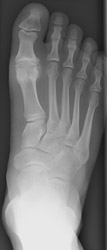

Osteoarthritis: Lateral View - Large dorsal osteophytes at 1st MTP jointOsteoarthritis: AP View - Large osteophytes and joint space narrowing at 1st MTP jointOSTEOARTHRITIS non-inflammatory deterioration of articular cartilage with articular surface and marginal bone formation.

Radiographic manifestations may include marginal osteophyte and subchondral bony cyst formation, eburnation, and interosseous joint space narrowing. First metatarsal phalangeal joint osteoarthritis is frequently associated with hallux valgus deformities. Calcaneal spurs, when manifested, are sharp and well defined.